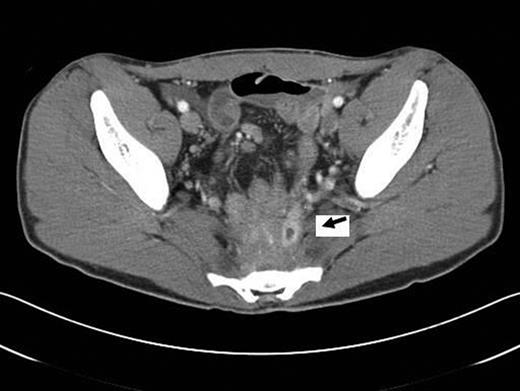

At the time of evaluation at our institution, he was afebrile and the laboratory tests, including inflammatory markers, were unremarkable. A computed tomography (CT) scan of the abdomen and pelvis showed a presacral fluid collection with a fistula between the pouch and the sacrum (Fig. 1). An MRI of the pelvis was performed and this revealed signs of osteomyelitis involving the S2–S4 vertebrae (Fig. 2). A laparotomy was performed and the ileal-anal pouch anastomosis was taken down, the sacrum was debrided leaving a large anterior bony defect. No omentum was available, so a 10 cm × 10 cm piece of Alloderm was used to cover the defect. The pouch fistula was excised and closed and the revised pouch re-anastomosed to the anus. The patient made an uneventful recovery and was discharged on the seventh postoperative day. Cultures from the sacral debrided tissue yielded Actinomyces spp. and a 12-week course of antibiotics (clindamycin) was commenced.

CT scan. Presacral air-fluid collection with a pouch-sacral fistula (arrow).